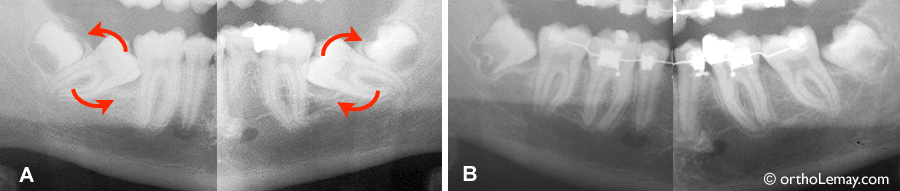

- Plusieurs dents sévèrement endommagées; les 4 premières molaires sont soit cariées, fracturées ou ont de larges réparations (amalgames) – (flèches rouges sur la photo).

- Étant donné le mauvais état des premières molaires, nous avons opté pour les faire extraire et fermer les espaces créés par ces extractions.

- Cette approche est inhabituelle mais très bénéfique dans ce cas. Ceci a évité à la patiente des frais dentaires importants qui auraient été nécessaires pour faire faire des traitements de canal, réparations, couronnes, etc. En fait, dans ce cas spécifique, l’économie réalisée par la patiente en faisant extraire les 4 molaires a couvert plus que les frais d’extraction et d’orthodontie!